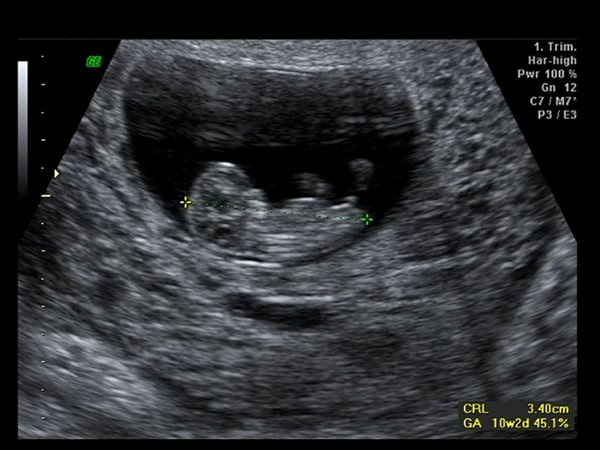

Har i dag været til scanning for første gang. (Lidt før tid - 10+1) og ville bare lige dele de dejlige billeder med jer. Den var meget livlig. Både ben og arme bevægede sig hele tiden

Er i den syvende himmel på sådan en dejlig solskinsdag